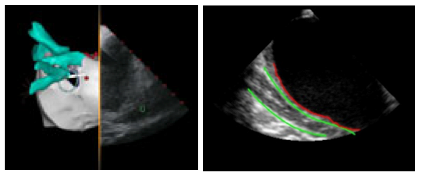

In collaborazione con la

Biosense Webster del gruppo Johnson & Johnson, produttrice del sistema Carto3®, il sistema di mapping 3D più diffuso e utilizzato per gli interventi di ablazione, e con il Dipartimento di Cardiologia dell’ l’Ospedale Santa Maria delle Croci di Ravenna, si sta sviluppando un sistema di monitoraggio dell'esofago dall'elaborazione dei dati acquisiti con il catetere intracardiaco ad US disponibile nel sistema, al fine di ridurre il rischio di lesioni all’esofago durante le procedure di ablazione.